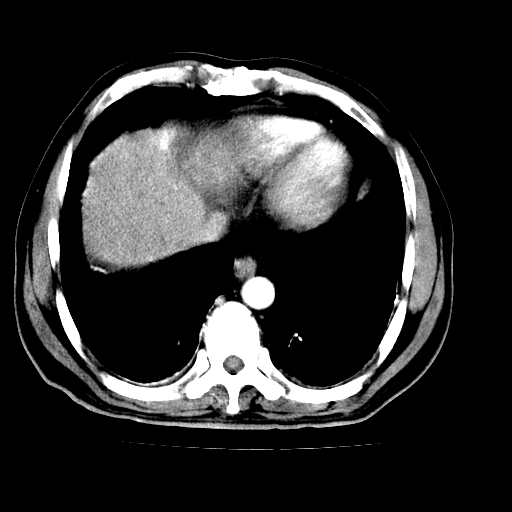

男,66岁,上腹部不适、黄染一周。彩超示:肝左叶占位,肝内胆管扩张,胆总管扩张,胆总管占位?

肝左叶不规则软组织肿块影,边缘不规整邻近肝实质受累分界不清;肝内胆管(左叶)明显扩张成“软藤状”,诊断:肝左叶胆管细胞癌。

肝左叶占位性病变,并胆管扩张,符合胆管细胞癌ct表现,门脉左支受累,左肾囊肿。窗宽太窄了,其他的看不清

左叶胆管细胞癌累及胆总管,门脉左支受侵,慢性胆囊炎胆结石,左肾小囊肿

胆囊缩小,其内胆汁浓缩,也提示梗阻部位应该位于胆囊管起始部以上或是胆囊管受累及,支持肝外胆管癌。